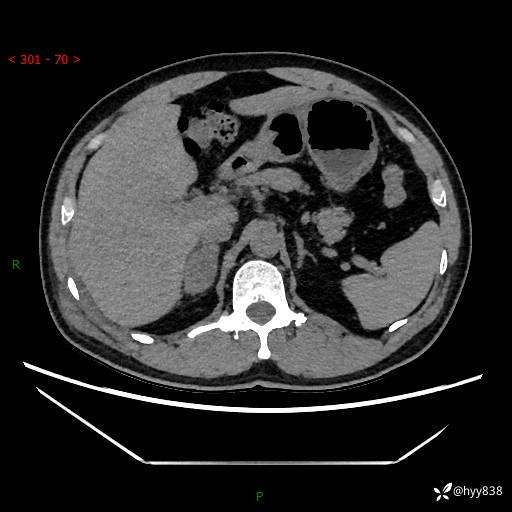

现病史:患者9月4日摔伤在深圳市宝安区中心医院行CT检查提示右侧肾上腺区结节(38*27mm),复查B超提示右侧肾上腺区可见一61*24mm异常低回声团,建议进一步检查。进一步完善增强CT后提示:右侧肾上腺区肿块及周围渗出改变,大致同前,考虑肾上腺腺瘤,不除外瘤内出血可能,否认阵发性头晕、头痛、出汗、乏力等不适,门诊以“ 右侧肾上腺肿瘤”收入住院。 起病来,患者精神、食欲、睡眠可,大便通畅,小便如上述,体力体重无明显改变。

肾上腺CT平扫

增强(动脉期+静脉期)